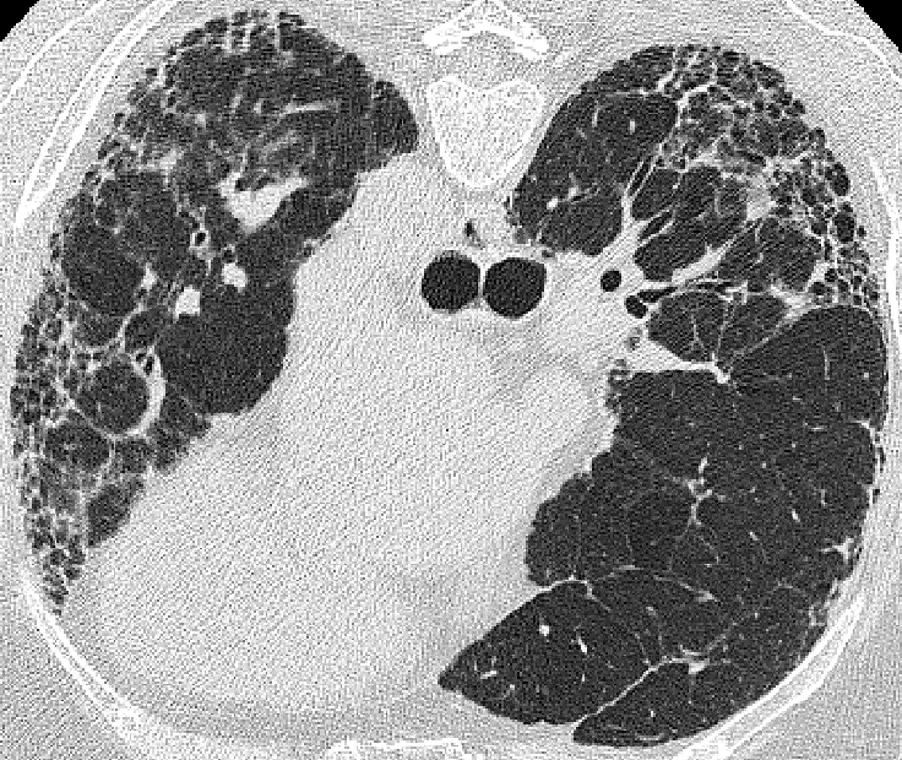

Quantitative Image Analysis (QIA) combine proprietary denoising with CT-based quantification of fibrotic lung disease, including lung volume and QILD metrics, to support precise, pattern-based evaluation of interstitial scarring.

- Quantitative Interstitial Lung Disease (QILD):

- Lung Fibrosis (QLF)

- Honeycombing (QHC)

- Ground Glass Opacity (GGO)